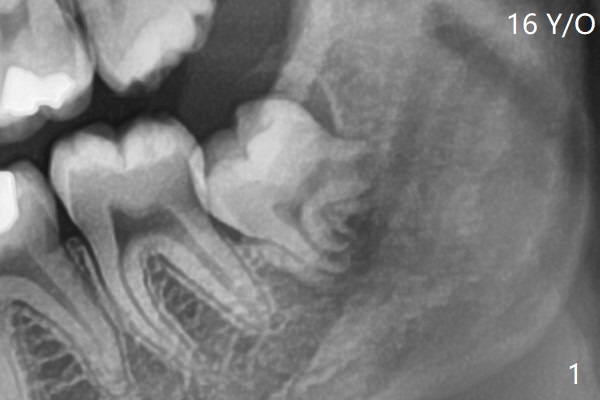

截骨后牙齿容易松动,然后切断两次,顺利拔除,放置Osteogen Plug,4-0 铬羊肠线缝合(图二)。近中牙槽嵴中断。